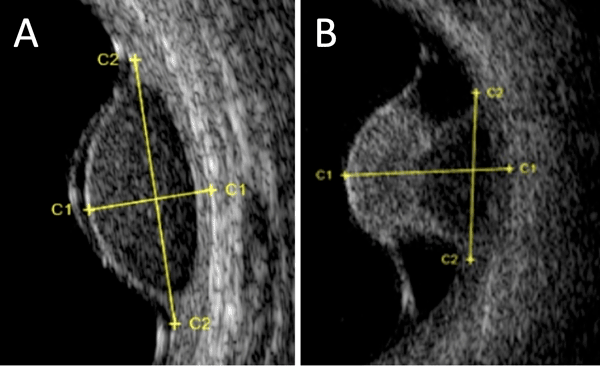

Mélanome choroïdien Diagnostic du mélanome choroïdien Il s'agit de la tumeur intraoculaire primitive la plus fréquente de l'adulte. Le mélanome uvéal peut toucher la choroïde (site le plus fréquent que nous décrirons ici), le corps ciliaire ou l'iris. Son incidence annuelle est d'environ 500-600 nouveaux cas par an en France. L'âge médian au diagnostic est de 62 ans mais il peut survenir à tout âge. Il touche généralement les sujets caucasiens, avec un surrisque parmi les personnes ayant les yeux bleus, pour des raisons non encore élucidées. Le diagnostic est clinique, ce qui est une singularité en oncologie, car l'obtention d'une preuve histologique par biopsie invasive exposerait à un risque de dissémination orbitaire. Il repose sur l'examen du fond d'œil et l'échographie oculaire. On observe une lésion choroïdienne en relief (Figures 1 et 2), de morphologie en dôme ou en champignon (Figure 3). La lésion est souvent pigmentée mais peut également être achrome (Figures 4 et 5), ce qui doit alors faire suspecter une métastase choroïdienne, avec réalisation d'un bilan d'extension complet, à la recherche d'une néoplasie primaire ayant métastasé à l'œil. Un décollement de rétine exsudatif peut être présent (Figure 6). Une hémorragie intravitréenne peut s'associer et masquer la tumeur. Ces deux présentations impliquent de devoir réaliser systématiquement une échographie oculaire en cas de décollement de rétine exsudatif sans déhiscence retrouvée, ou en cas d'hémorragie intravitréenne. En effet, une éventuelle chirurgie intraoculaire par vitrectomie sur un mélanome uvéal méconnu peut entraîner une dissémination tumorale.

Figure 3 Échographie oculaire montrant un mélanome choroïdien en dôme (A) et en champignon (B).